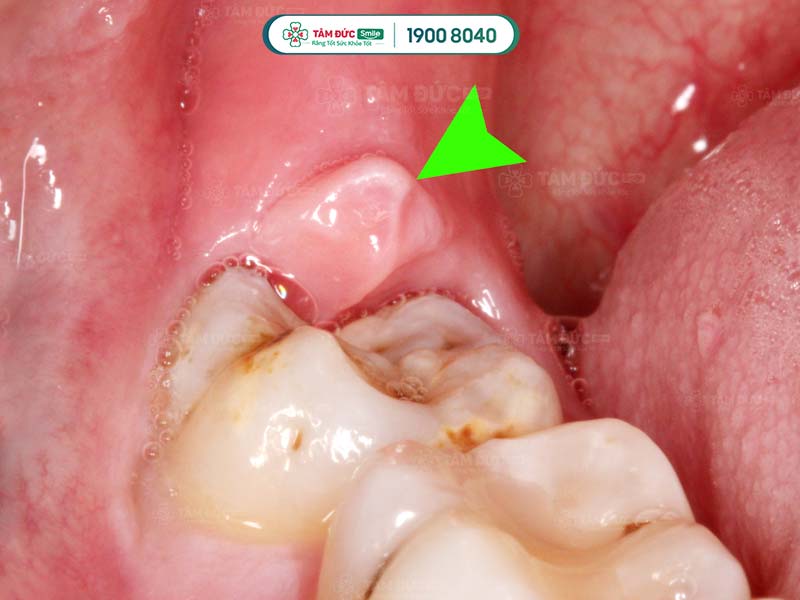

2.3. Răng khôn mọc lệch

Răng khôn sẽ mọc khi Quý khách ở tuổi trưởng thành. Vì là răng mọc sau cùng nên dễ xuất hiện tình trạng mọc lệch, hay mọc đâm vào răng số 7… Khi mọc răng khôn, vùng nướu trong cùng xuất hiện tình trạng sưng viêm và đau nhức.

Răng khôn mọc lệch làm sưng nướu răng